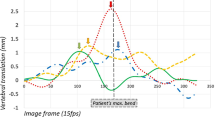

Only graphs in which all vertebral angles in the 5 runs coincided visually were regarded as reliable and therefore entered into the data pool. Two observers independently inspected all graphs for inclusion. Only those that met this criterion and were adjacent to vertebrae whose graphs did too, were analysed. The analysis consisted of subtracting the vertebral angle sequences of adjacent segments from each other in all combinations (i.e. L1a-L2a, L1a-L2b, L1b-L2b etc) to give inter-vertebral angles throughout the motion. This gave 25 individual inter-vertebral angles for each of 120 images in each motion sequence. These were represented graphically with the median as a solid line and each of the individual 25 points as a scatter plot (Figure 7), showing the full range and variation of each vertebral angle subtraction.

Forty-three motion segments (vertebral pairs) from L3 to L5 could be reliably tracked in side-bending motion for both first and second screenings. These provided inter-vertebral motion graphs from 43 adjacent vertebrae whose individual analyses coincided over 5 separate markings (Figure 6). Figure 8 shows an example of sidebending inter-vertebral motion graphs at the L4-5 level between observers and between screenings.

The motion patterns were all regular and in the direction of trunk motion, but not always symmetrical, as can be seen in Figure 8. The inter-observer variation (RMS) of intervertebral rotational range was 1.86° for side-bending and 1.94° for flexion-extension. The intra-subject biological variation for side-bending range was 2.75° and 2.91° for Observers 1 and 2 respectively (Table 4).